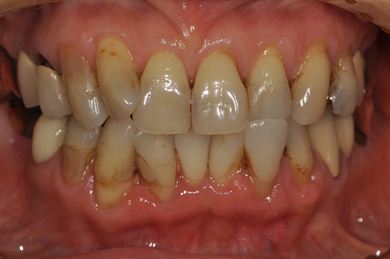

抜歯即日スピードインプラント+セラミック治療

| 性別/年齢 | 女性 / 52歳 | ||||||||||||||||||||||||||||||||

| 主訴 | 引っ越しで治療が途中になっている歯の治療と、他の歯にもトラブルが起こったため相談したい。 | ||||||||||||||||||||||||||||||||

| 治療内容 | インプラント2本(抜歯即日スピードインプラント)、ハイブリッドセラミッククラウン5本(セラミック用土台2本)、ハイブリッドセラミックインレー1本 | ||||||||||||||||||||||||||||||||